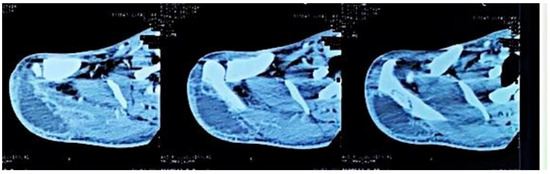

Figure 3. Axial CT sections of the shoulder, showing the lytic lesion of the distal ½ of the right scapular spine.

Computed tomography of the right shoulder showed a lytic lesion of the right scapula with cortical rupture associated with scapular osteomyelitis (Figure 3, Figure 4 and Figure 5). The lesion was complicated by a deltoid abscess measuring 75 × 29 mm and extending over 105 mm (Figure 4), without joint effusion.

Clinically, osteoarticular TB can mimic other inflammatory and neoplastic bone lesions such as pyogenic osteomyelitis, fungal infection, multiple myeloma and metastatic disease [8]. For our case, the presence of any other germ was ruled out by pus culture and even multiplex PCR. The radiological features of skeletal TB are not specific. They may vary from lytic lesions and periarticular osteoporosis to bone marrow oedema, joint effusion, tenosynovitis and soft tissue collections [9], as in our patient, in whom a CT scan of the shoulder revealed bone lysis of the ½ distal scapular spine with cortical rupture and deltoid collection.